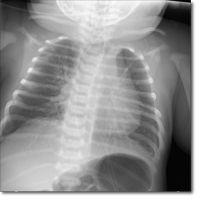

Recién nacida mujer, con peso de 3080 gramos. A la exploración se aprecia un saco íntegro que...

Torres del Pino M, González Vila L.

02 diciembre 2025